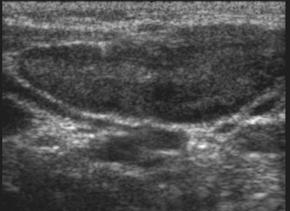

Инструментальные методы включали ультразвуковое исследование (эхографию) лимфоузлов. Использовались аппараты с конвексными и линейными датчиками с частотой 7,МГц с цветным допплеровским картированием (ЦДК). Данный метод применялся в группе исследования. При помощи УЗИ, в В-режиме оценивали размер лимфоузла, его форму, соотношение слоев, однородность эхоструктуры. Проводили оценку кровотока в области ворот, наличие или отсутствие очагов деструкции. При эхографии лимфоузлы - это образования овальной или округлой формы, расположенные в подкожной клетчатке и мягких тканях. Обычно хорошо дифференцируются основные части: корковый, мозговой слой и ворота лимфоузла, с впадающими сосудами. Эхоструктура лимфоузлов представлена на рис. 2

А Б

Рис. 2. А) Структура лимфоузла в норме,

Б) Структура при остром лимфадените